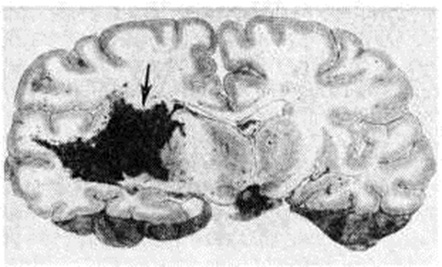

Геморрагический инсульт, как правило, возникает при заболеваниях, протекающих с повышенным артериальное давление. Это обусловлено тем, что сосудистые кризы (смотри полный свод знаний), характерные для гипертонической болезни (смотри полный свод знаний) и артериальной гипертензии (смотри полный свод знаний Гипертензия артериальная), приводят к морфологический изменениям стенок внутримозговых сосудов с нарушением их проницаемости — плазматическому пропитыванию (рисунок 1), некрозам (рисунок 2), образованию микроаневризм (рисунок 3) и их разрывам. Разрыв врождённых артериальных и артериовенозных аневризм может протекать на фоне нормального давления. Преимущественная локализация и характер геморрагий определяются особенностями ангиоархитектоники различных отделов мозга. При гипертонической болезни наиболее тяжёлым изменениям подвергаются сосуды подкорковых узлов и зрительного бугра. Это объясняется отхождением глубоких ветвей под прямым углом от средней мозговой артерии, являющейся продолжением внутренней сонной артерии, и незначительным числом анастомозов сосудов в этой области. В связи с этим на вскрытии кровоизлияния наиболее часто (40%) обнаруживаются в подкорковых узлах с распространением в прилежащее белое вещество (так называемый латеральные кровоизлияния, то есть расположенные латерально от внутренней капсулы, рисунок 4). Второе место по частоте (16%) занимают обширные кровоизлияния, разрушающие подкорковые узлы, внутреннюю капсулу, зрительный бугор (так называемый смешанные кровоизлияния — рисунок 5). Кровоизлияния в зрительный бугор (так называемый медиальные — рисунок 6) составляют 10%, в мозжечок — 6—10%, в мост мозга — 5% от общего числа внутримозговых геморрагий. Кровоизлияния только в белое вещество полушарий мозга встречаются крайне редко. Подразделение полушарных кровоизлияний на латеральные, медиальные и смешанные имеет особое значение в связи с хирургическим лечением геморрагического Инсульт.

Кровоизлияния типа гематомы сопровождаются образованием полости, содержащей жидкую кровь или свёртки крови; они составляют 85% внутримозговых кровоизлияний, наиболее часто развиваются в подкорковых узлах, реже в мозжечке. Основной механизм развития гематомы — разрыв патологически изменённого сосуда (рисунок 7). Формирование гематомы идёт путём раздвигания кровью вещества мозга с перемещением его участков, что возможно благодаря резервным пространствам (желудочки, подпаутинное пространство). Размеры гематомы при этом превышают объем разрушенного кровью вещества, сдавление окружающих отделов незначительно; лишь при кровоизлиянии в мозжечок сдавление вещества мозга весьма существенно в связи с анатомическими особенностями задней черепной ямки (рисунок 8).

Кровоизлияния типа геморрагического пропитывания возникают преимущественно в зрительных буграх, реже в мосту мозга и составляют 15% внутримозговых кровоизлияний. Они являются результатом слияния мелких очагов кровоизлияний, возникающих путём диапедеза из мелких сосудов, имеют вид очагов красного цвета, дряблой консистенции и в силу внешнего сходства иногда напоминают геморрагический инфаркт. В первые часы Инсульт нарушается проницаемость сосудов на границе с кровоизлиянием, развивается отёк; кровь распространяется по ходу нервных волокон. К концу первых суток наблюдаются лейкостазы и лейкодиапедез, размеры очага увеличиваются за счёт диапедезных геморрагий и некробиотических изменений в отёчном веществе мозга. Через двое суток начинается процесс репарации — появление зернистых шаров и гипертрофированных астроцитов; позже образуется вал из астроглии и новообразованных сосудов, кровь подвергается гемолизу, появляются макрофаги с гемосидерином, образуются аргирофильные и коллагеновые волокна. Исходом кровоизлияния может быть формирование глиомезодермального рубца или кисты, содержащих гемосидерин (рисунок 9). В 80—85% кровоизлияний на вскрытии выявляется прорыв крови в желудочки, значительно реже — в подпаутинное пространство. В последнее кровь может также проникнуть из четвёртого желудочка. Первичные вентрикулярные геморрагии нетравматического генеза — явление казуистическое. При разрыве врождённых аневризм артерий основания мозга возникают первичные субарахноидальные кровоизлияния, которые обычно локализуются на базальной поверхности или в латеральной борозде; иногда кровь проникает в субдуральное пространство; часто повреждается вещество мозга (субарахноидально-паренхиматозные кровоизлияния). Расположение гематом, образующихся при этом, зависит от локализации аневризмы, обычно это базальный отдел лобной доли или височная область. В части случаев при незначительном субарахноидально-паренхиматозном кровоизлиянии возможен массивный прорыв крови в желудочки (рисунок 10), что иногда ошибочно диагностируется как первичное вентрикулярное кровоизлияние.